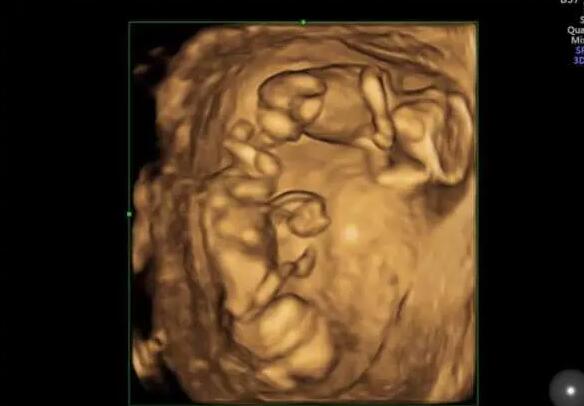

婴儿床上,双胞胎宝贝粉嫩的小手紧紧攥着妈妈的手指,那么温暖那么有爱。谁会想到,不久前兄弟俩刚经历一场生死之战,90余天在医护人员的精心治疗和呵护下,勇敢的宝贝们创造生命奇迹,回到爸爸妈妈的怀抱。15日,这对超早产双胞胎宝宝终于康复出院,他们也是西安交大一附院成功救治的西北最小胎龄超早产双胞胎试管婴